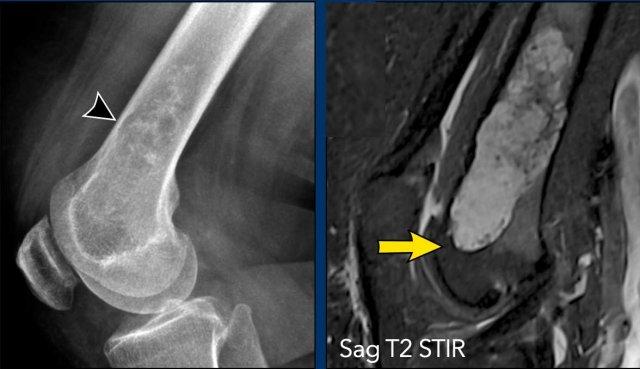

Hình ảnh

Phim X-quang cho thấy một tổn thương tiêu xương ở đầu xa xương đùi chứa các vôi hóa dạng bỏng ngô điển hình và có hình ảnh xói mòn vỏ xương phía trước (đầu mũi tên).

Trên MRI mặt phẳng đứng dọc, chúng ta có thể nhận thấy rằng khối u lớn hơn vùng vôi hóa trên phim X-quang, với kích thước 8 cm.

Khối u tăng tín hiệu trên T2 STIR và chứa nhiều ổ có tín hiệu thấp, tương ứng với các vôi hóa chất nền sụn trên phim X-quang.

Kết luận

Vì không có phản ứng màng xương hay khối phần mềm, các dấu hiệu này phù hợp với chẩn đoán ACT.

Bệnh nhân tiếp tục được theo dõi.